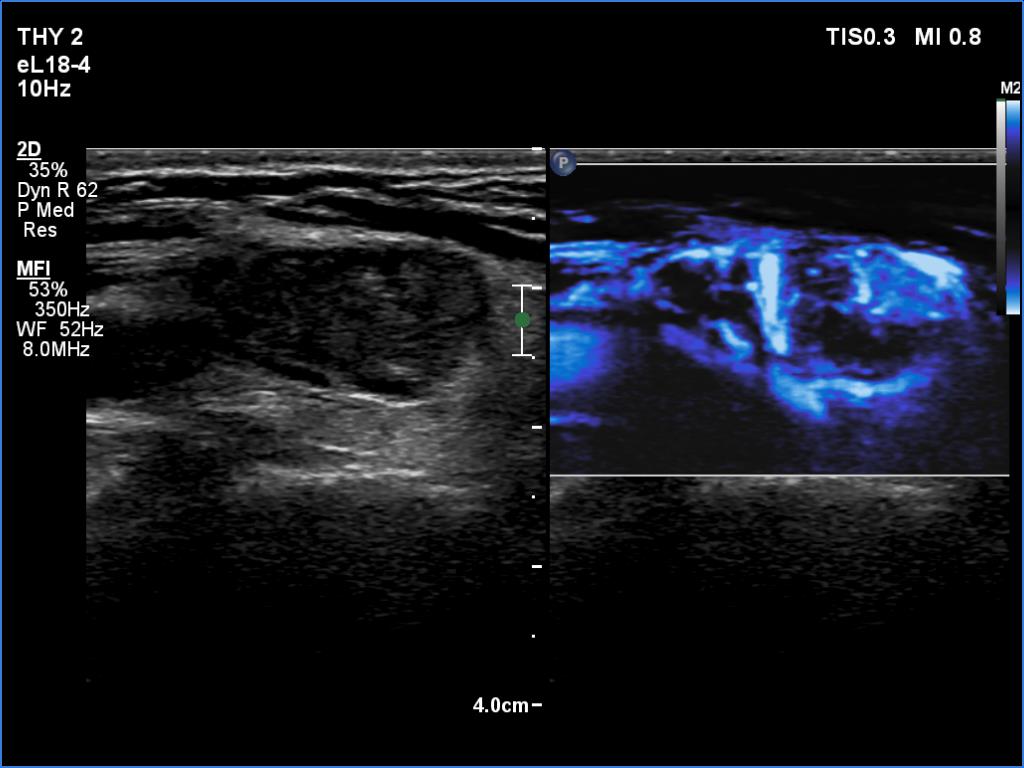

Graves' disease - case 169

Follow-up investigation 6 months after first visit (ultrasonographic picture 8)

Left lobe, longitudinal scan, microflow imaging. There are no vessels within the mass in question.